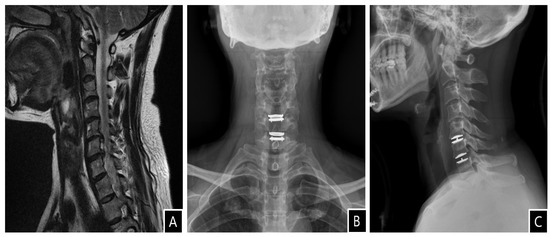

Vertebral artery dissection (VAD) is a rare vascular cause of acute stroke. Although VAD may be classified as spontaneous or traumatic, it is increasingly recognized that trivial mechanical stress typically precipitates this potentially dangerous condition. Herein, we report a rare case of VAD and acute stroke following anterior cervical decompression and artificial disc replacement (ADR). To our knowledge, there have been no other cases of acute vertebrobasilar stroke caused by VAD following anterior cervical decompression and ADR. This case highlights that, although rare, acute vertebrobasilar stroke may occur after the anterior cervical approach.